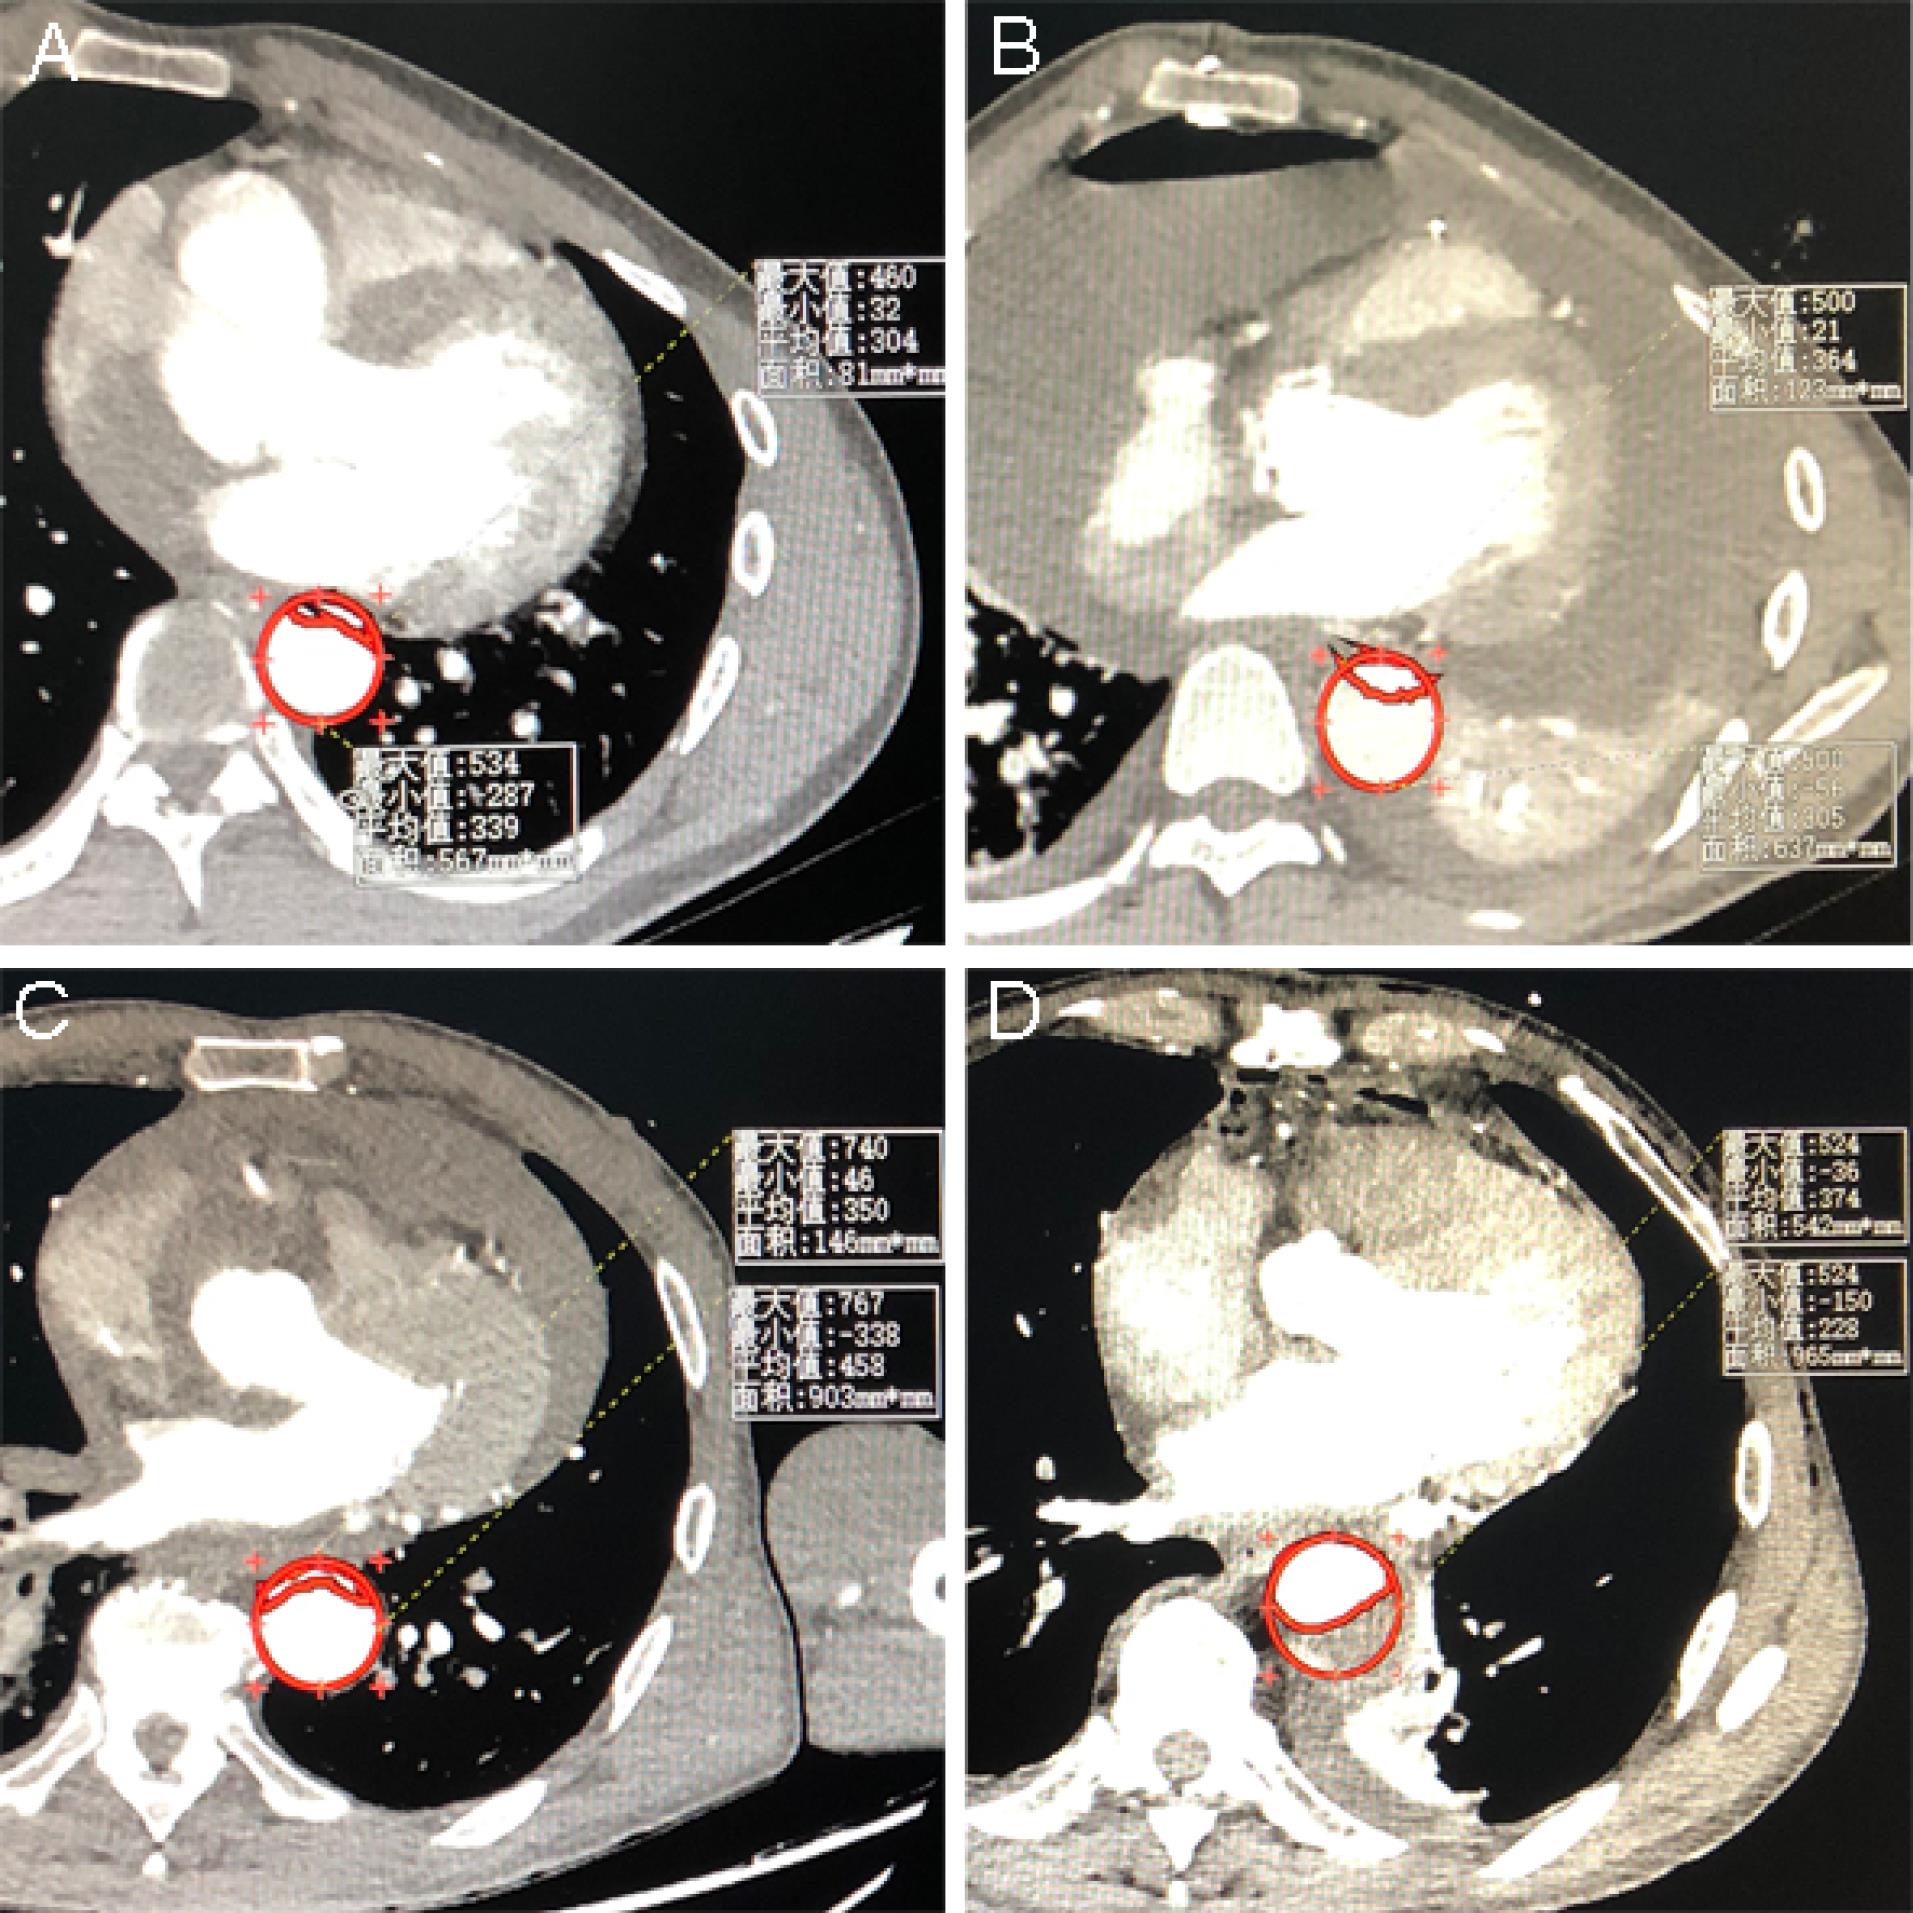

Multivariable logistic regression analysis showed that the perfusion method was significantly correlated with postoperative MFLA ratio. The postoperative MFLA ratio on the descending thoracic aorta were reduced more in PCC group than that in PC group with 0.35 ± 0.11 and 0.44 ± 0.13, respectively (Figure 3, P < 0.001). Moreover, postoperative involvement of the ostium of the dissected branch arteries on CTA including coeliac trunk artery, superior mesenteric artery, renal artery and Iliac artery was notably decreased in PCC group (Figure 4). There were a lower incidence rate of hepatic dysfunction and RRT in PCC group compared with those in PC group (15.5% vs. 39.8%, P < 0.001; 10.3% vs. 20.5%, P = 0.012, respectively). There was also a lower serum inflammation response (hs-CRP and IL-6) and anaerobic metabolism (lactate) in 24 hours after procedure in PCC group than those in PC group. The in-hospital survival, the duration of ICU and hospital stay was similar, but APACHE II score and mechanical ventilation time was lower in PCC than that in PC group, respectively (Table 3).

The comparison between preoperative and postoperative MFLA ratio on the descending thoracic aorta. The preoperative and postoperative MFLA ratio calculated by imaging assistant software system was 0.71 ± 0.14 (Figure 2A) and 0.44 ± 0.13 (Figure 2B) in PC group, respectively. The preoperative and postoperative MFLA ratio was 0.70 ± 0.14 (Figure 2C) and 0.36 ± 0.11 (Figure 2D) in PCC group, respectively (postoperative MFLA ratio between PC and PCC group, P < 0.001). MFLA: maximum false lumen area ratio in descending thoracic aorta; PC: peripheral cannulation; PCC: peripheral-to-centric cannulation

Figure 3.